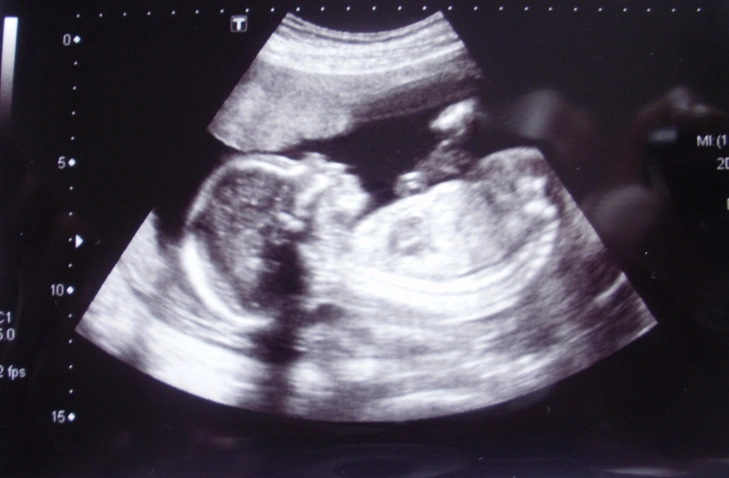

• Early pregnancy ultrasound (available at all clinics)

• Typically, weeks 7-9

• Confirms the pregnancy, fetal heartbeat, gestational age, and possible multiple pregnancy

• Nuchal translucency (NT) scan and early anatomy screening (available in Kuopio)

• Weeks 11+0 - 13+6

• Measures nuchal translucency to assess chromosomal risk and evaluates early fetal structures

• Second-trimester ultrasound  (available in Kuopio)

• Weeks 16-18

• Evaluates early fetal anatomy and development, placental location, and amniotic fluid

• Fetal anatomy scan (available in Kuopio)

• Weeks 18-21+6

• Detailed scan to assess fetal anatomy, monitor growth, and detect potential abnormalities

• 3D/4D Pregnancy ultrasound (available in Kuopio)

• Typically, weeks 24-30

• Visualizes movements, facial features, and positioning in a real-time scan. Evaluates growth, development, and amniotic fluid.

• NIPT test  (available at all clincs)

• Done as a blood test from the mother after week 10

• Screens for risk of most common chromosome abnormalities (trisomy 21, 18, and 13) and prediction of baby’s gender if requested.